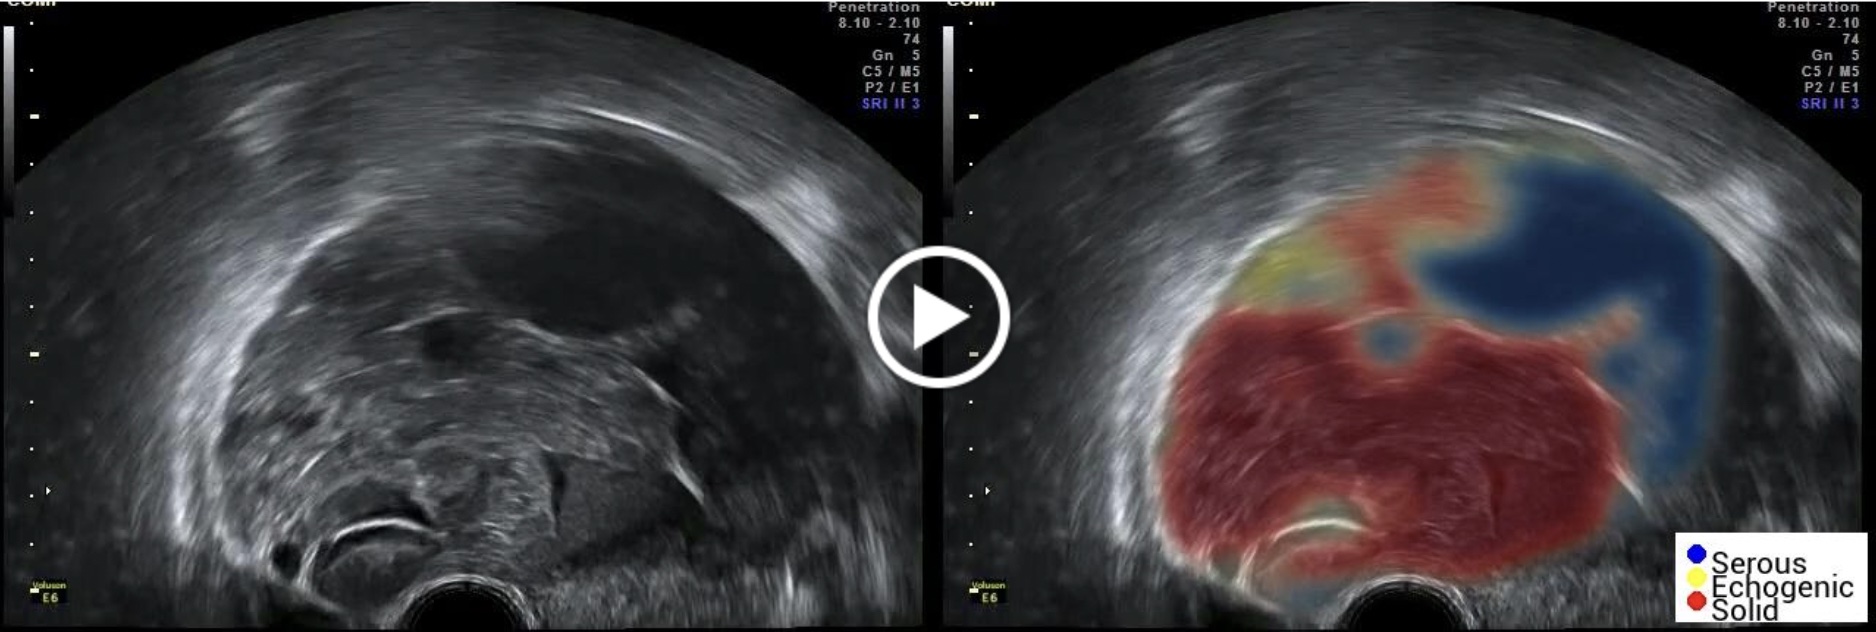

SynDiag ha sviluppato due SaMD denominati OvAi Focus e OvAi X, Software as a Medical Device, basati su Intelligenza artificiale (IA) e disponibili stand alone in cloud per il medico ginecologo. I due dispositivi potranno essere utilizzati congiuntamente, per un’elaborazione automatica e operatore indipendente, a supporto della diagnosi del tumore ovarico.

OvAi Focus consente di identificare e descrivere l’anatomia di una lesione dell’ovaio. L’output di OvAi Focus è una nuova ecografia, aumentata con una mappa in codice colore che evidenzia le aree anatomiche e una lista di keyword descrittive. OvAi Focus, già Classe I secondo la direttiva UE 93/42/CEE, oggi è pronto per la registrazione al nuovo MDR 2017/745 in Classe I: lo scopo previsto è quello di studio della anatomia e la sua prestazione clinica è misurabile tramite indicatori di qualità, quantità e tempestività del dato disponibile al medico ginecologo per la descrizione anatomica durante la refertazione. L’ impatto positivo sul PDTA è stato provato grazie alla collaborazione con l’A.O. Mauriziano di Torino, Reparto di Ginecologia, il quale guida una sperimentazione clinica che ha arruolato più di 1000 casi clinici, di cui 200 sono utilizzati come test set indipendente. I modelli di AI seguono quindi una fase di training e di validazione con un approccio di k-fold cross validation e le loro performance vengono poi calcolate sul test set.

OvAi Focus ha mostrato un’accuratezza descrittiva superiore a quella del medico esperto (accuracy per keyword “Tipo di Lesione”: OvAi Focus 84%; media medici esperti di 61% – da validazione sperimentale; ground truth è la descrizione da referto ecografico e da anatomia patologica).